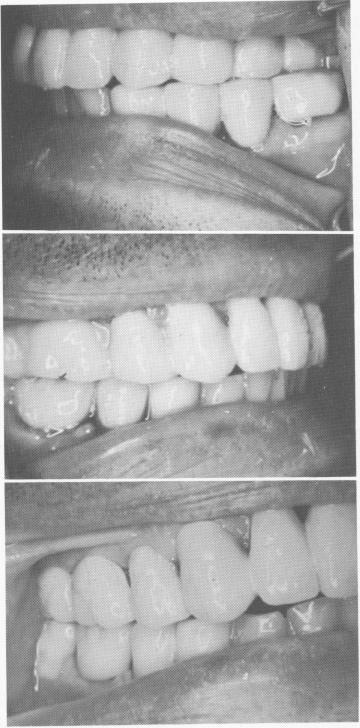

Fig. 15-47. The upper prosthesis is cemented with hard cement.

1 Upper endosseous blade implant prosthesis cemented